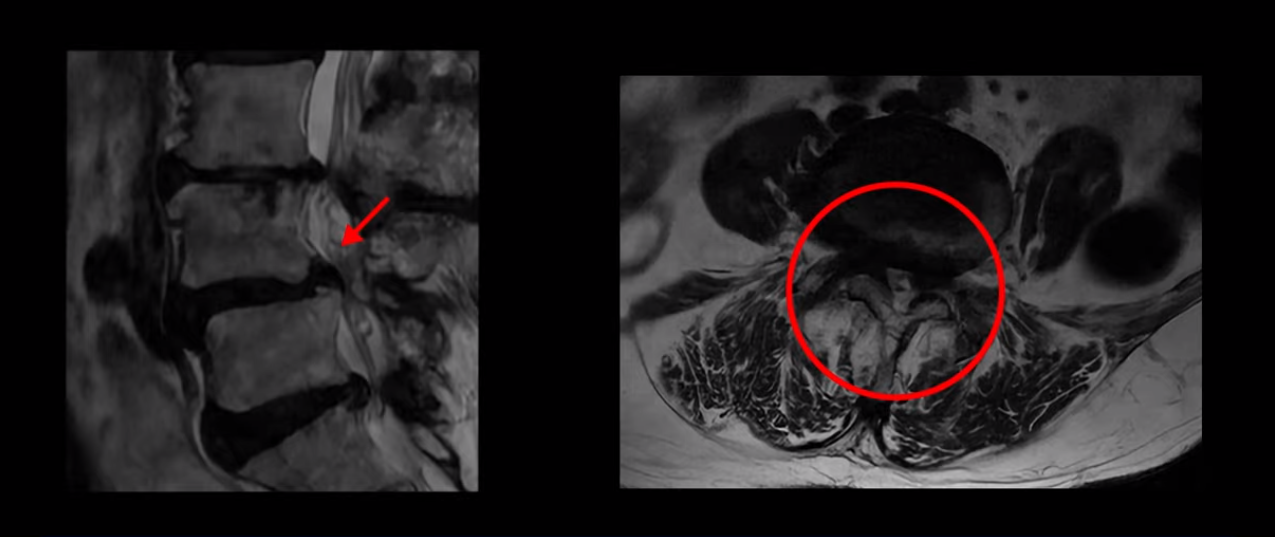

제가 먼저 이분 MRI를 보고 설명해 드린 후 어떻게 이런 분들을 수술 없이 허리 기능재활치료로 호전시킬 수 있는지 자세히 설명드리겠습니다. 이분 허리가 보시다시피 여러 마디가 퇴행되어 있고

4번 5번에는 뼈가 밀려 나간 전방전위증도 있습니다.

4번 5번 마디를 자세히 보면 심한 중심성 협착이 있어서 신경 구멍이 매우 좁아져 있습니다.

또 신경 가지가 빠져나가는 추간공도 매우 좁아져 있습니다.

그래서 양쪽 엉덩이가 아프고 다리는 발바닥까지 저리고 아프면서 발을 줄로 묶어놓은 것 같고 다리의 힘도 빠져 걷기가 어렵습니다.